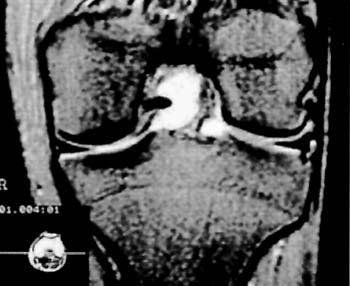

Los estudios Rx, y de TAC fueron en todos los casos negativos, en cambio, se destaca la RNM como metodo fundamental para su diagnostico. (Fig 1)

El mismo se caracteriza por su ubicacion central adosado al Ligamento Cruzado Posterior desplazando hacia lateral al Ligamento Cruzado Anterior.

Su densidad lo asemeja como un tumor con caracteristicas liquidas y su forma multilobulada ocupa practicamente el intercondilo femoral (Fig 2-3-4) En T2 es facilmente distinguible como una masa homogenea que ocupa todo el contorno del condilo femoral interno.

Figura 1